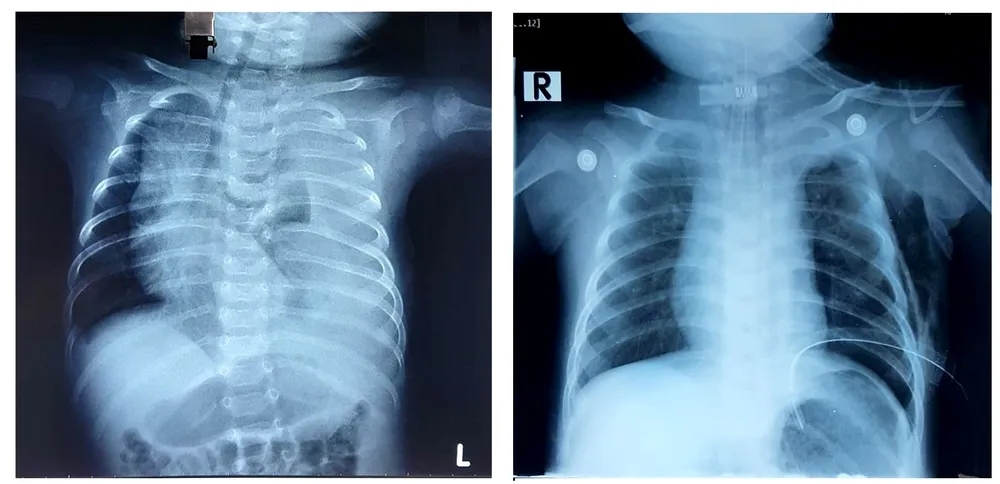

Bệnh nhi nhập viện trong tình trạng khó thở nặng, phim chụp X quang phổi của bé xuất hiện tràn dịch màng phổi (là tình trạng có dịch lỏng chưa rõ bản chất trong khoang màng phổi) bên trái lượng nhiều, gây nên tình trạng chèn ép nhu mô phổi khiến bé không thở được.

Ngay lập tức, bệnh nhi được đặt dẫn lưu màng phổi, các bác sĩ ghi nhận rất nhiều dịch đục như sữa chảy ra từ khoang màng phổi. Kết quả xét nghiệm dịch màng phổi cho thấy bệnh nhi bị một tình trạng rò dịch dưỡng trấp nghi do rò từ ống ngực vào khoang màng phổi